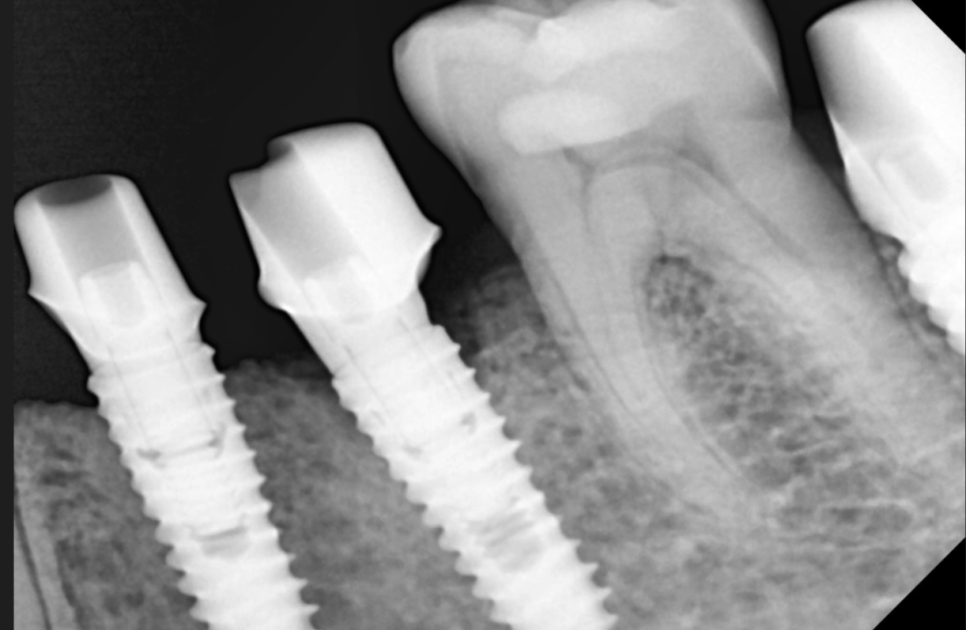

어금니 빠짐 부분을

3차원적으로 분석을 하고

치료 계획을 세워드렸습니다.

23.02.23

망월동 임플란트 수술 직후 사진입니다.

환자분이 한 번에 끝내고 싶다고 하셨는데요.

미리 ct를 통해 분석하고 수술을 해서

당일에 8개 임플란트를 심었지만

1시간 정도 걸렸습니다.